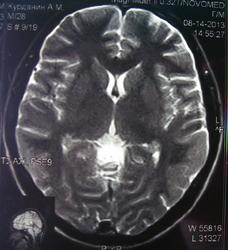

При изучении МРТ снимков головного мозга невролог указала на наличие маленьких очажков на коре головного мозга, порекомендовав обратиться за лечением к нейрохирургам. Голова также продолжает болеть, еще стали кисти рук неметь и прочие симптомы. Можете ли вы указать, имеются ли эти маленькие очажки на коре головного мозга и где именно?

Алексей, очагов достоверно не вижу, а вот на верхнечелюстную пазуху нужно обратить внимание-есть ее воспалительные изменения в виде утолщения слизистой.